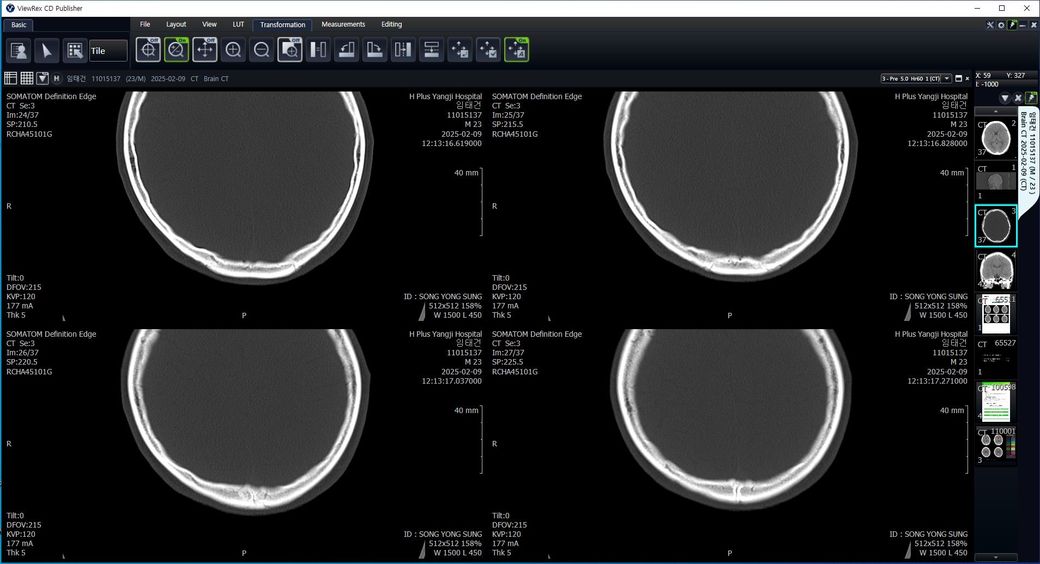

두개골 수술 또는 골절 의심되는 상황인데 엑스레이와 ct사진을 한번 봐주실 수 있나요?

2~3일 정도 기억이 없었는데 그때 머리를 다쳤는지 바로 x-ray와 ct를 찍어봤는데 한번 봐주실 수 있을까요? 진단 목적이 아닌 확인 목적입니다

빨갛게 동그라미 친 곳은 금속물질이 의심도는 부근입니다

• 4번 째 사진